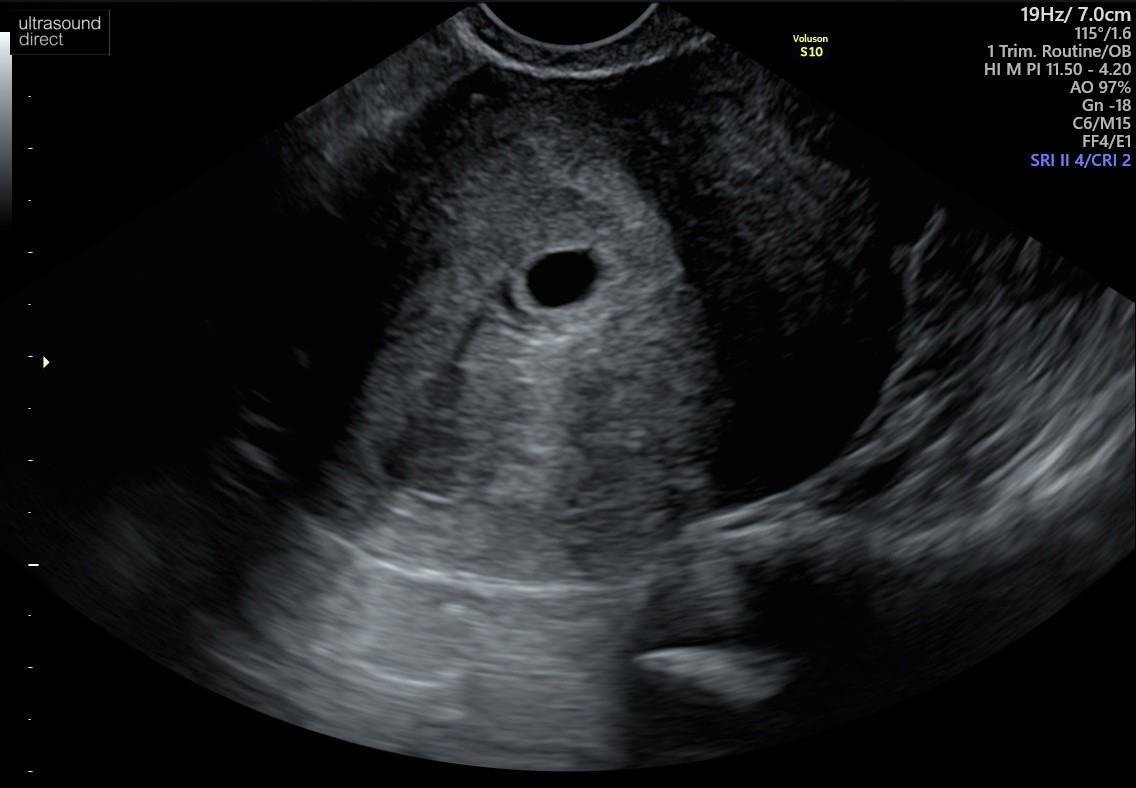

Witam , jestem w Uk - stad moje mega obawy chyba. Ostatnia miese miałam 7/08. Test pozytywny 4/09 w dzień spodziewanej miesiączki. Według obliczeń poszliśmy na usg w 7+6 tyg (25.09). Babeczka robiąc usg wykryła puste jajo płodowe z nawiązką krwi obok jaja. Powiedziała ze może to być puste, małe jajo płodowe albo 5 tydz ciąży dopiero, z tym ze nie jest widoczne ciałko żółte. Dwa dni po badaniu plamienia różowe , potem brązowe, bol brzucha pojechaliśmy do szpitala - dalej pusto ale mówią , plamienia to normalka, bol brzucha to normalka No i czekać za dwa tyg scan. Według moich obliczeń mega niemożliwością jest żebyśmy byli w piątym tyg dopiero bo sex uprawialiśmy 19/08 (20/08 wypadała ovulacja) prosze bez ocianiania ale potem nie mieliśmy sexu do 3/9 dzień nastepny robiłam test który wyszedł pozytywnie. Ja rozumiem ze może się wszystko poprzesuwać ale cykle mam co 28 dni, regularne. No i te plamienia teraz z bolącymi plecami i podbrzuszem. Zamartwiam się totalnie. Mial ktoś taka sytuacje ? Kiedy wszystko wydaje się kalendarzykowo a jednak te 2 wielkie tyg wszystko się przesunęło ??

A to z mojego skanu (25/09)